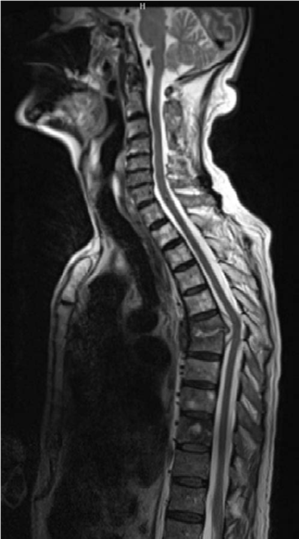

Spine structured oral questions2: Infection (epidural abscess) EXAMINER : A 68-year-old man with a past histo…